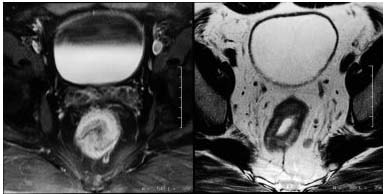

Rektum ve prostat incelemelerinde daha ayrıntılı görüntü oluşturmak amacıyla anüsten sokularak rektuma özel bir anten yerleştirilebilir. Ancak teknolojik gelişmeler ile sadece karın üzerine yerleştirilen özel antenler ile de benzer kalitede inceleme yapılabilmektedir. Özellikle kalın barsak tümörlerinde MR, kolonoskopi ile görülen tümörlerin barsak duvarı ve etrafındaki dokulara olan yayılımını belirlemek amacıyla kullanılır. İnce dilimler olarak tanımlanabilecek kesitler ile her düzlemde farklı görüntüler alarak kitlelerin yaygınlığını belirlemek ve tedaviyi planlamak amacıyla kullanılır.